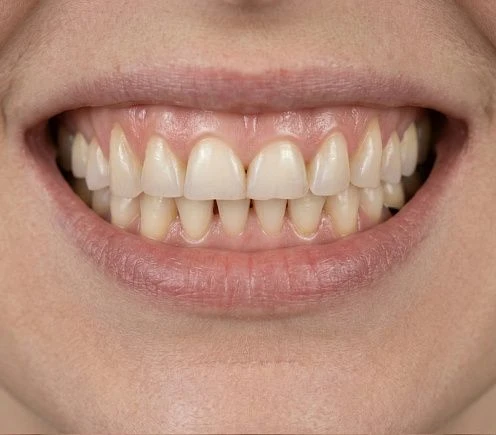

Наши работы